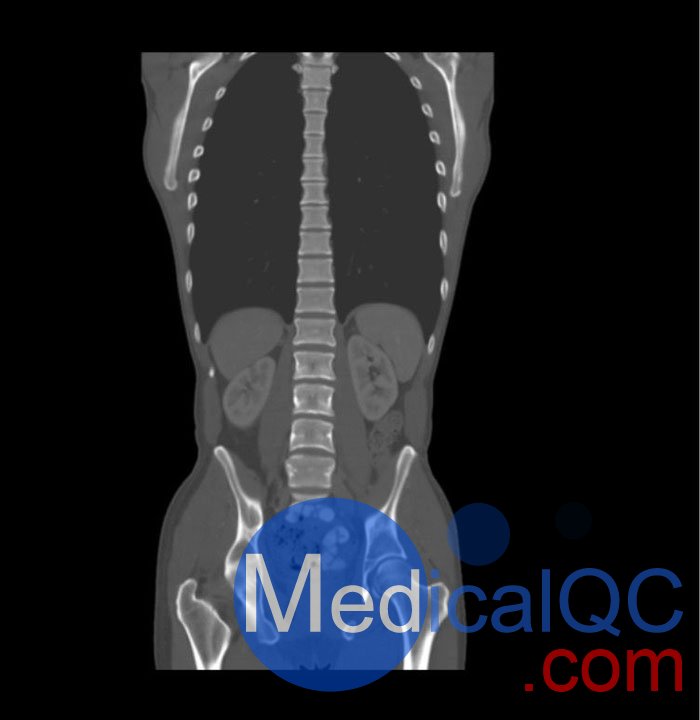

WEK57-01門靜脈期軀干模體,WEK57-01軀干模型模擬了門靜脈期的造影劑增強(qiáng)胸部、腹部和骨盆。它覆蓋了會陰的第二胸椎。

右側(cè)有髂淋巴結(jié)腫塊。

真實模擬脈管系統(tǒng)、骨骼和軟組織,包括肺、心臟、肝臟、膽囊、胰腺、脾臟、腎上腺、腎臟、胃、小腸、結(jié)腸、膀胱和前列腺。

右側(cè)髂外淋巴結(jié)腫塊。

WEK57-01門靜脈期軀干模體,WEK57-01軀干模型成像效果圖: